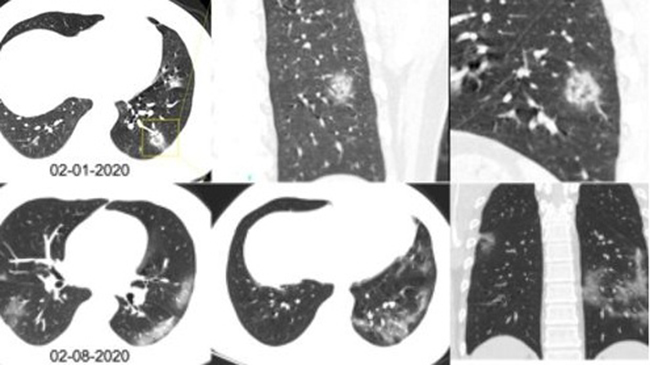

Đây là hình ảnh chụp CT phổi của một phụ nữ 33 tuổi ở bệnh viện Lan Châu, Trung Quốc. Cô nhập viện trong tình trạng sốt và ho trong 5 ngày, bác sĩ phát hiện số lượng bạch cầu của cô thấp và có dấu hiệu nhiễm trùng phổi. Bản quét CT cho thấy có các mảng trắng giống như thủy tinh bị mờ nằm ở thùy phải, sau đỉnh thùy trái.

Paras Lakhani, một bác sĩ X-quang tại Đại học Thomas Jefferson, người không tham gia vào nghiên cứu nhưng kiểm tra các hình ảnh, nói với trang Business Insider. "Đây là chất lỏng trong không gian phổi". Các nhà nghiên cứu cũng thấy rằng các mảng trắng trên phổi của người phụ nữ rõ rệt hơn trong hình ảnh thứ 2, được chụp lại sau 3 ngày sau lần đầu tiên. (Ảnh: Business insider)